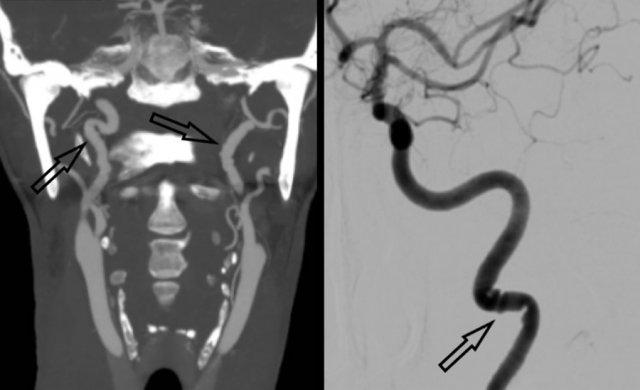

Rò động-tĩnh mạch màng cứng (dAVF) nằm ở xoang sigma phải được xác định bằng 4D-CTA và DSA.

4D-CTA bên trái, hình ảnh MIP trừ nền theo chiều bên cho thấy ngấm thuốc sớm bất thường của xoang sigma (mũi tên trắng) phù hợp với dAVF.

Động mạch chẩm phì đại được xác định là mạch nuôi (mũi tên đen).

DSA bên phải, bơm thuốc cản quang chọn lọc vào động mạch cảnh ngoài cho thấy động mạch chẩm phì đại và ngoằn ngoèo (mũi tên đen).

Dẫn lưu tĩnh mạch của xoang sigma vào tĩnh mạch cảnh (mũi tên trắng).